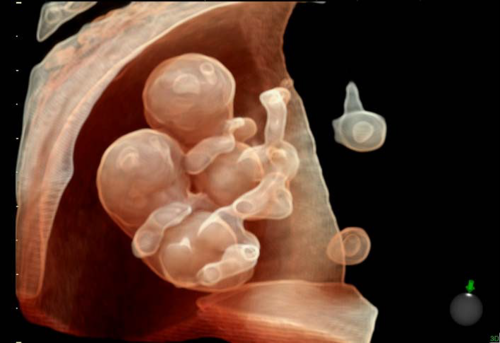

3D-4D ultrasound of a fetus imaged with a GE Volusion E10 system. It shows the yoke sac.